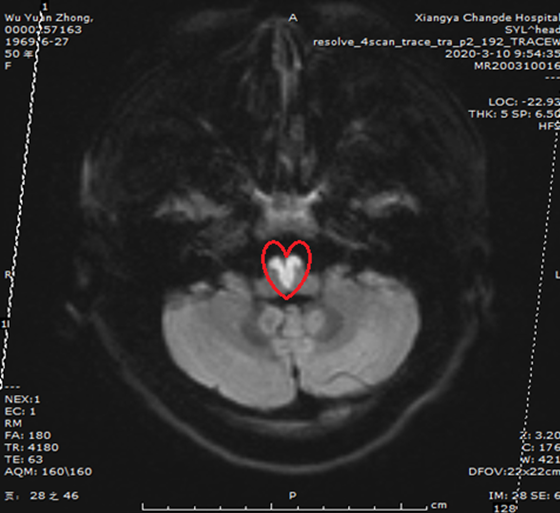

近日,来自张家界的吴女士突发脑梗死被湘雅常德医院神经内科收治入院。经脑部磁共振检查,图像上竟呈现出一个完美的“爱心”形,这便是导致吴女士四肢瘫痪,言语不能的罪魁祸首! 3月2日,50岁的吴女士...